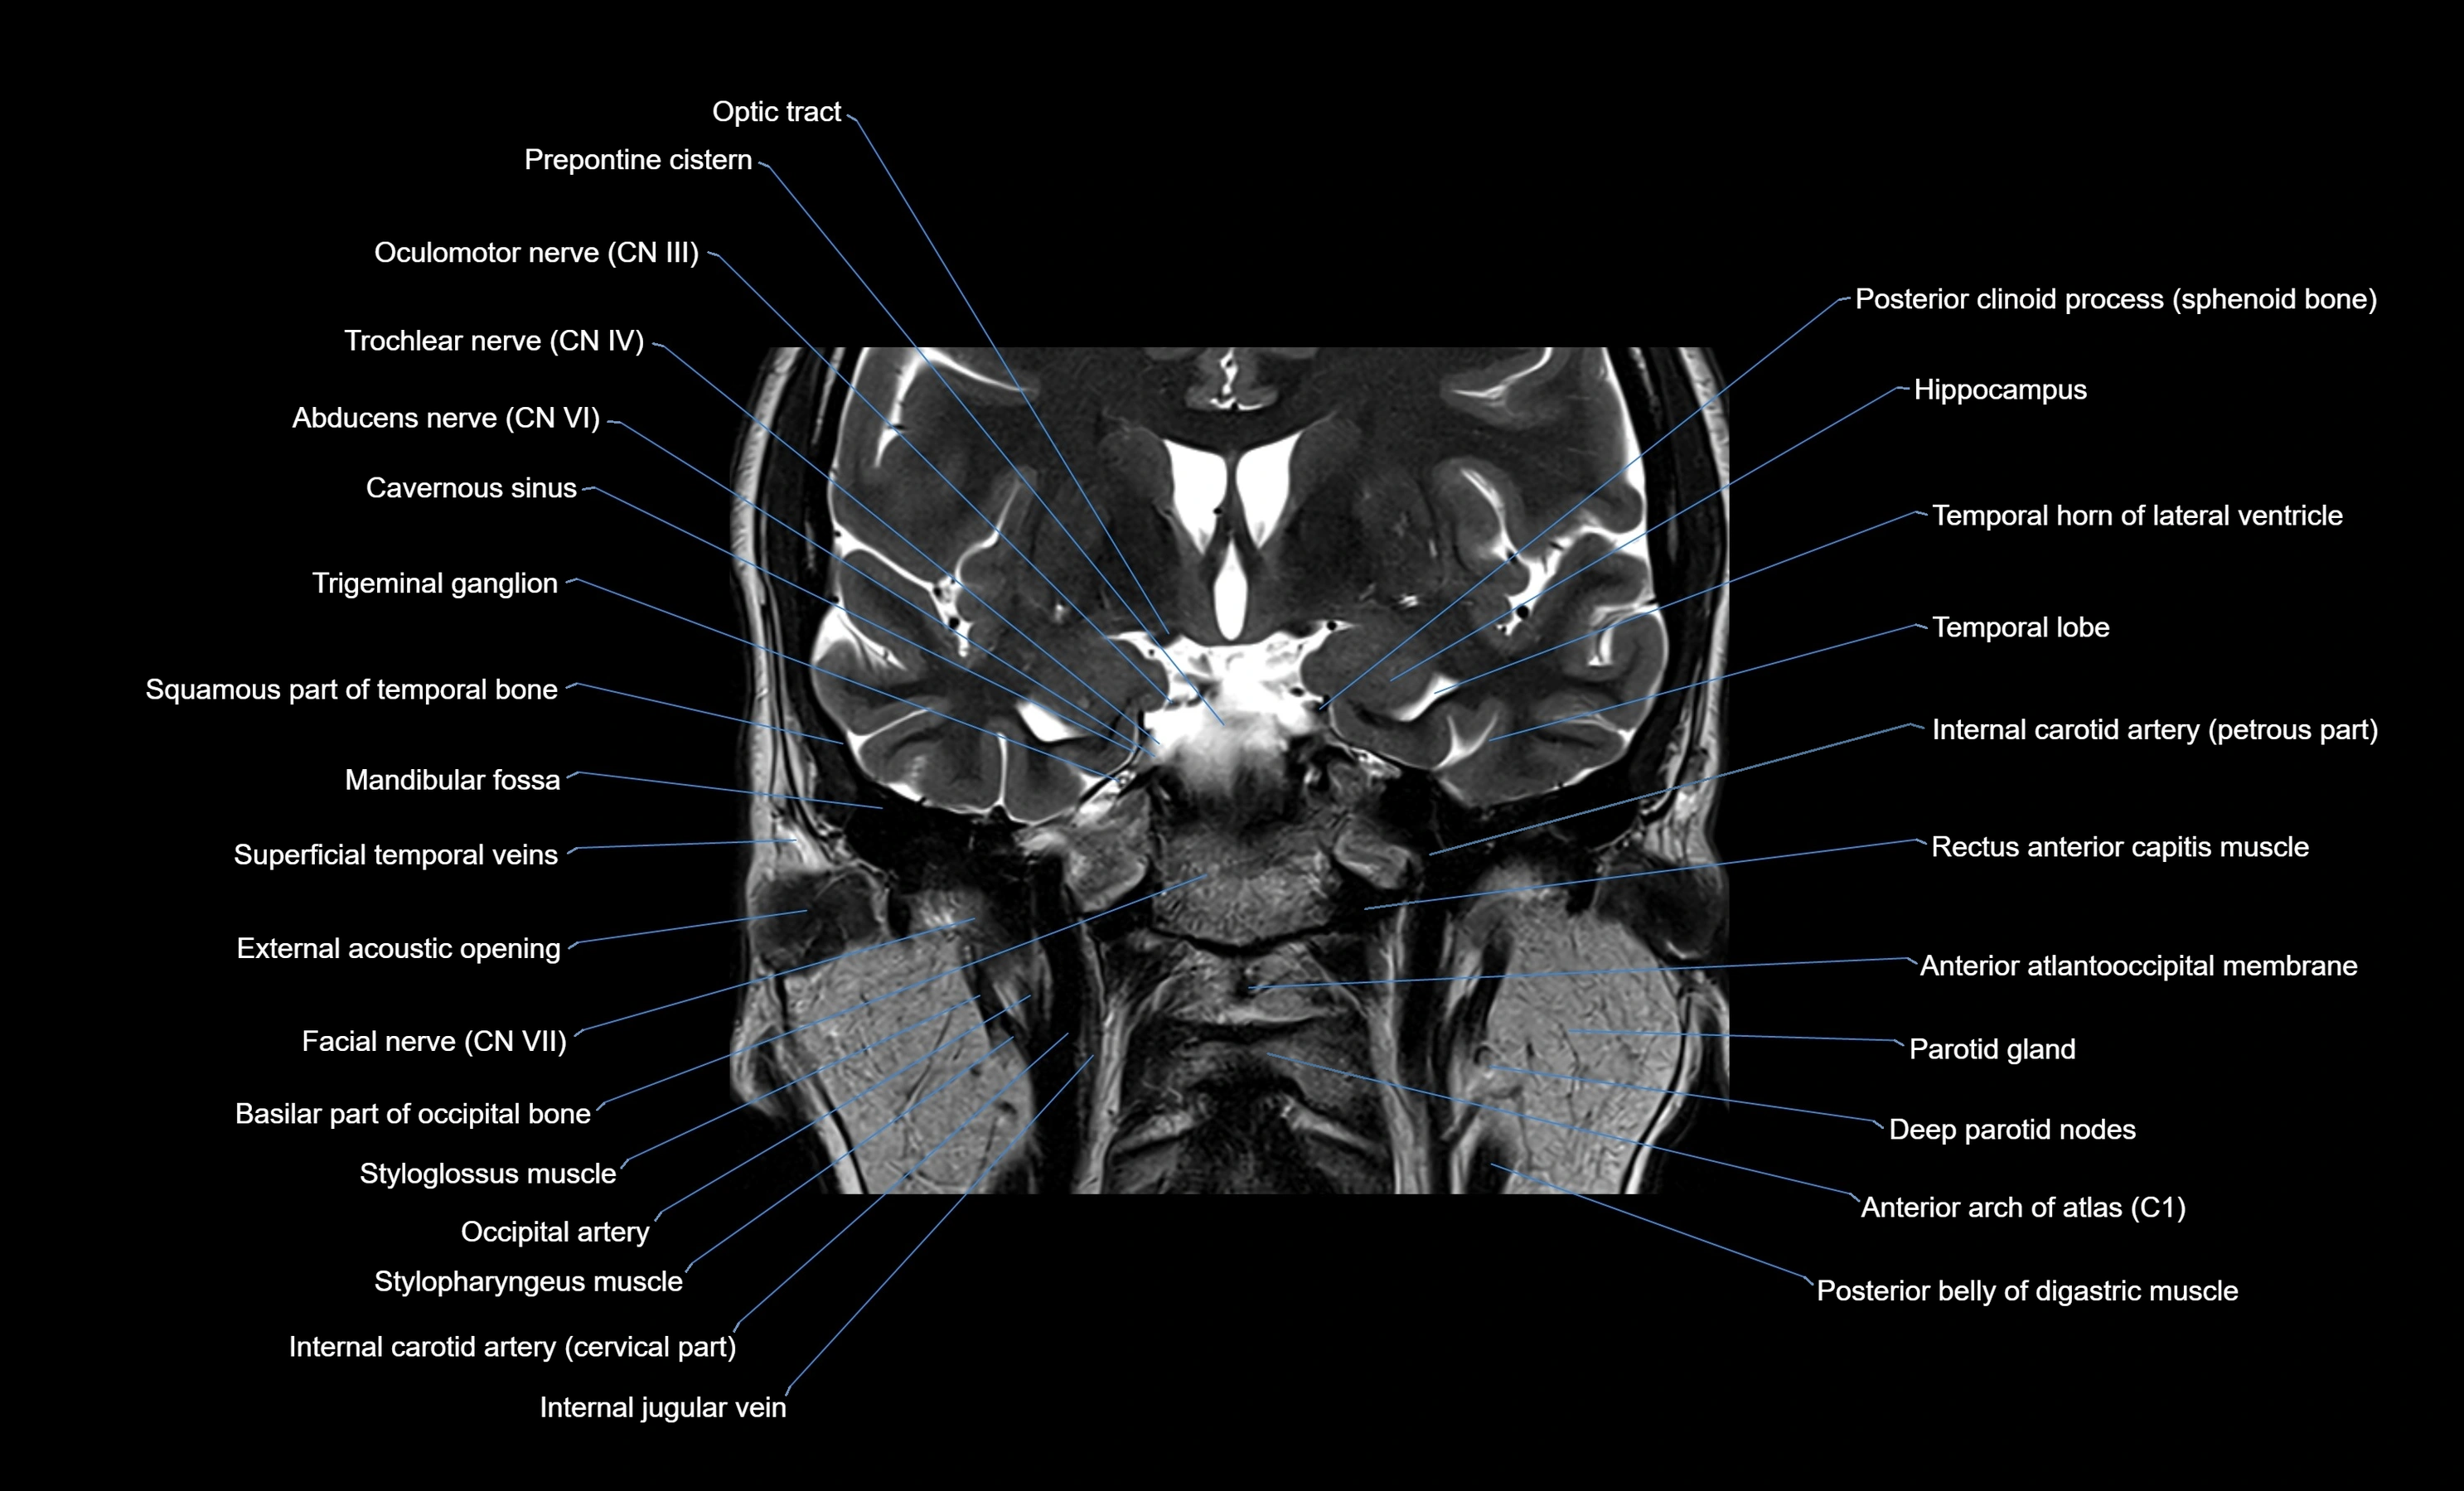

MRI images